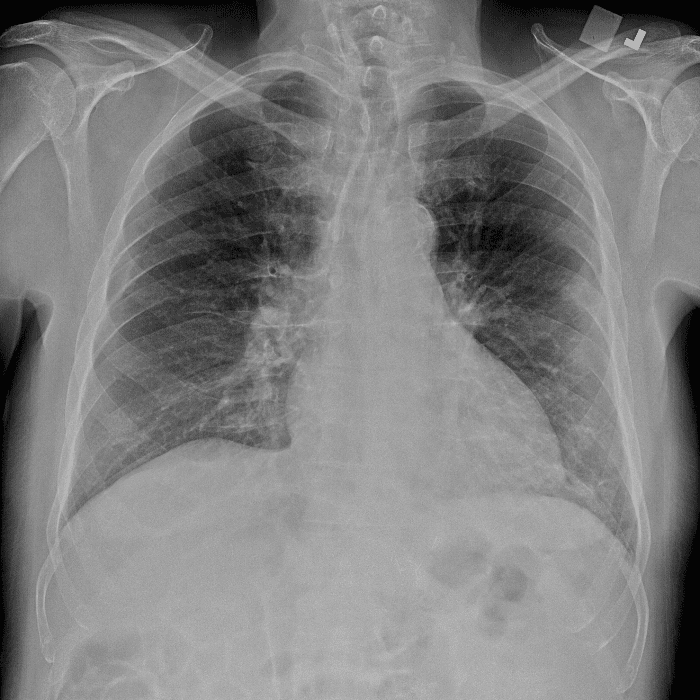

Practice Cases